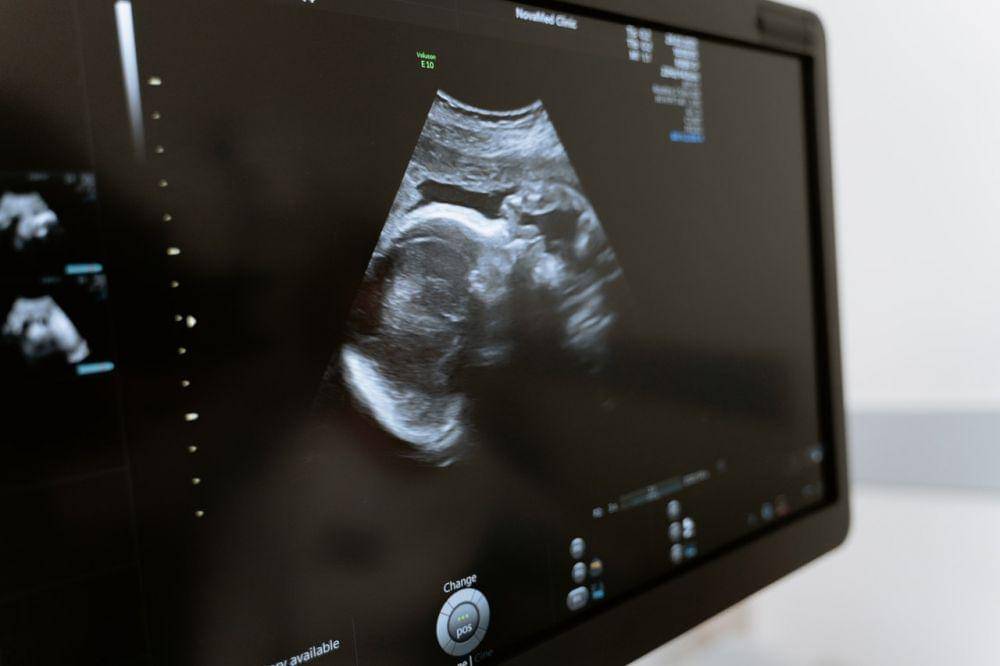

1. Ultrasonografi

Ultrasonografi atau yang lebih dikenal dengan USG merupakan skrining yang dilakukan menggunakan gelombang suara untuk membuat gambar bayi di dalam rahim. USG digunakan untuk menentukan ukuran dan posisi bayi dan menemukan kemungkinan kelainan pada struktur tulang dan organ lain.

Sementara itu, ultrasonografi khusus, yaitu Nuchal Translucency Ultrasound (NT) dilakukan untuk mengukur jumlah cairan bening di bagian belakang leher bayi. Jumlah cairan bening di atas normal merupakan tanda adanya kelainan kromosom, seperti down syndrome atau cacat jantung.